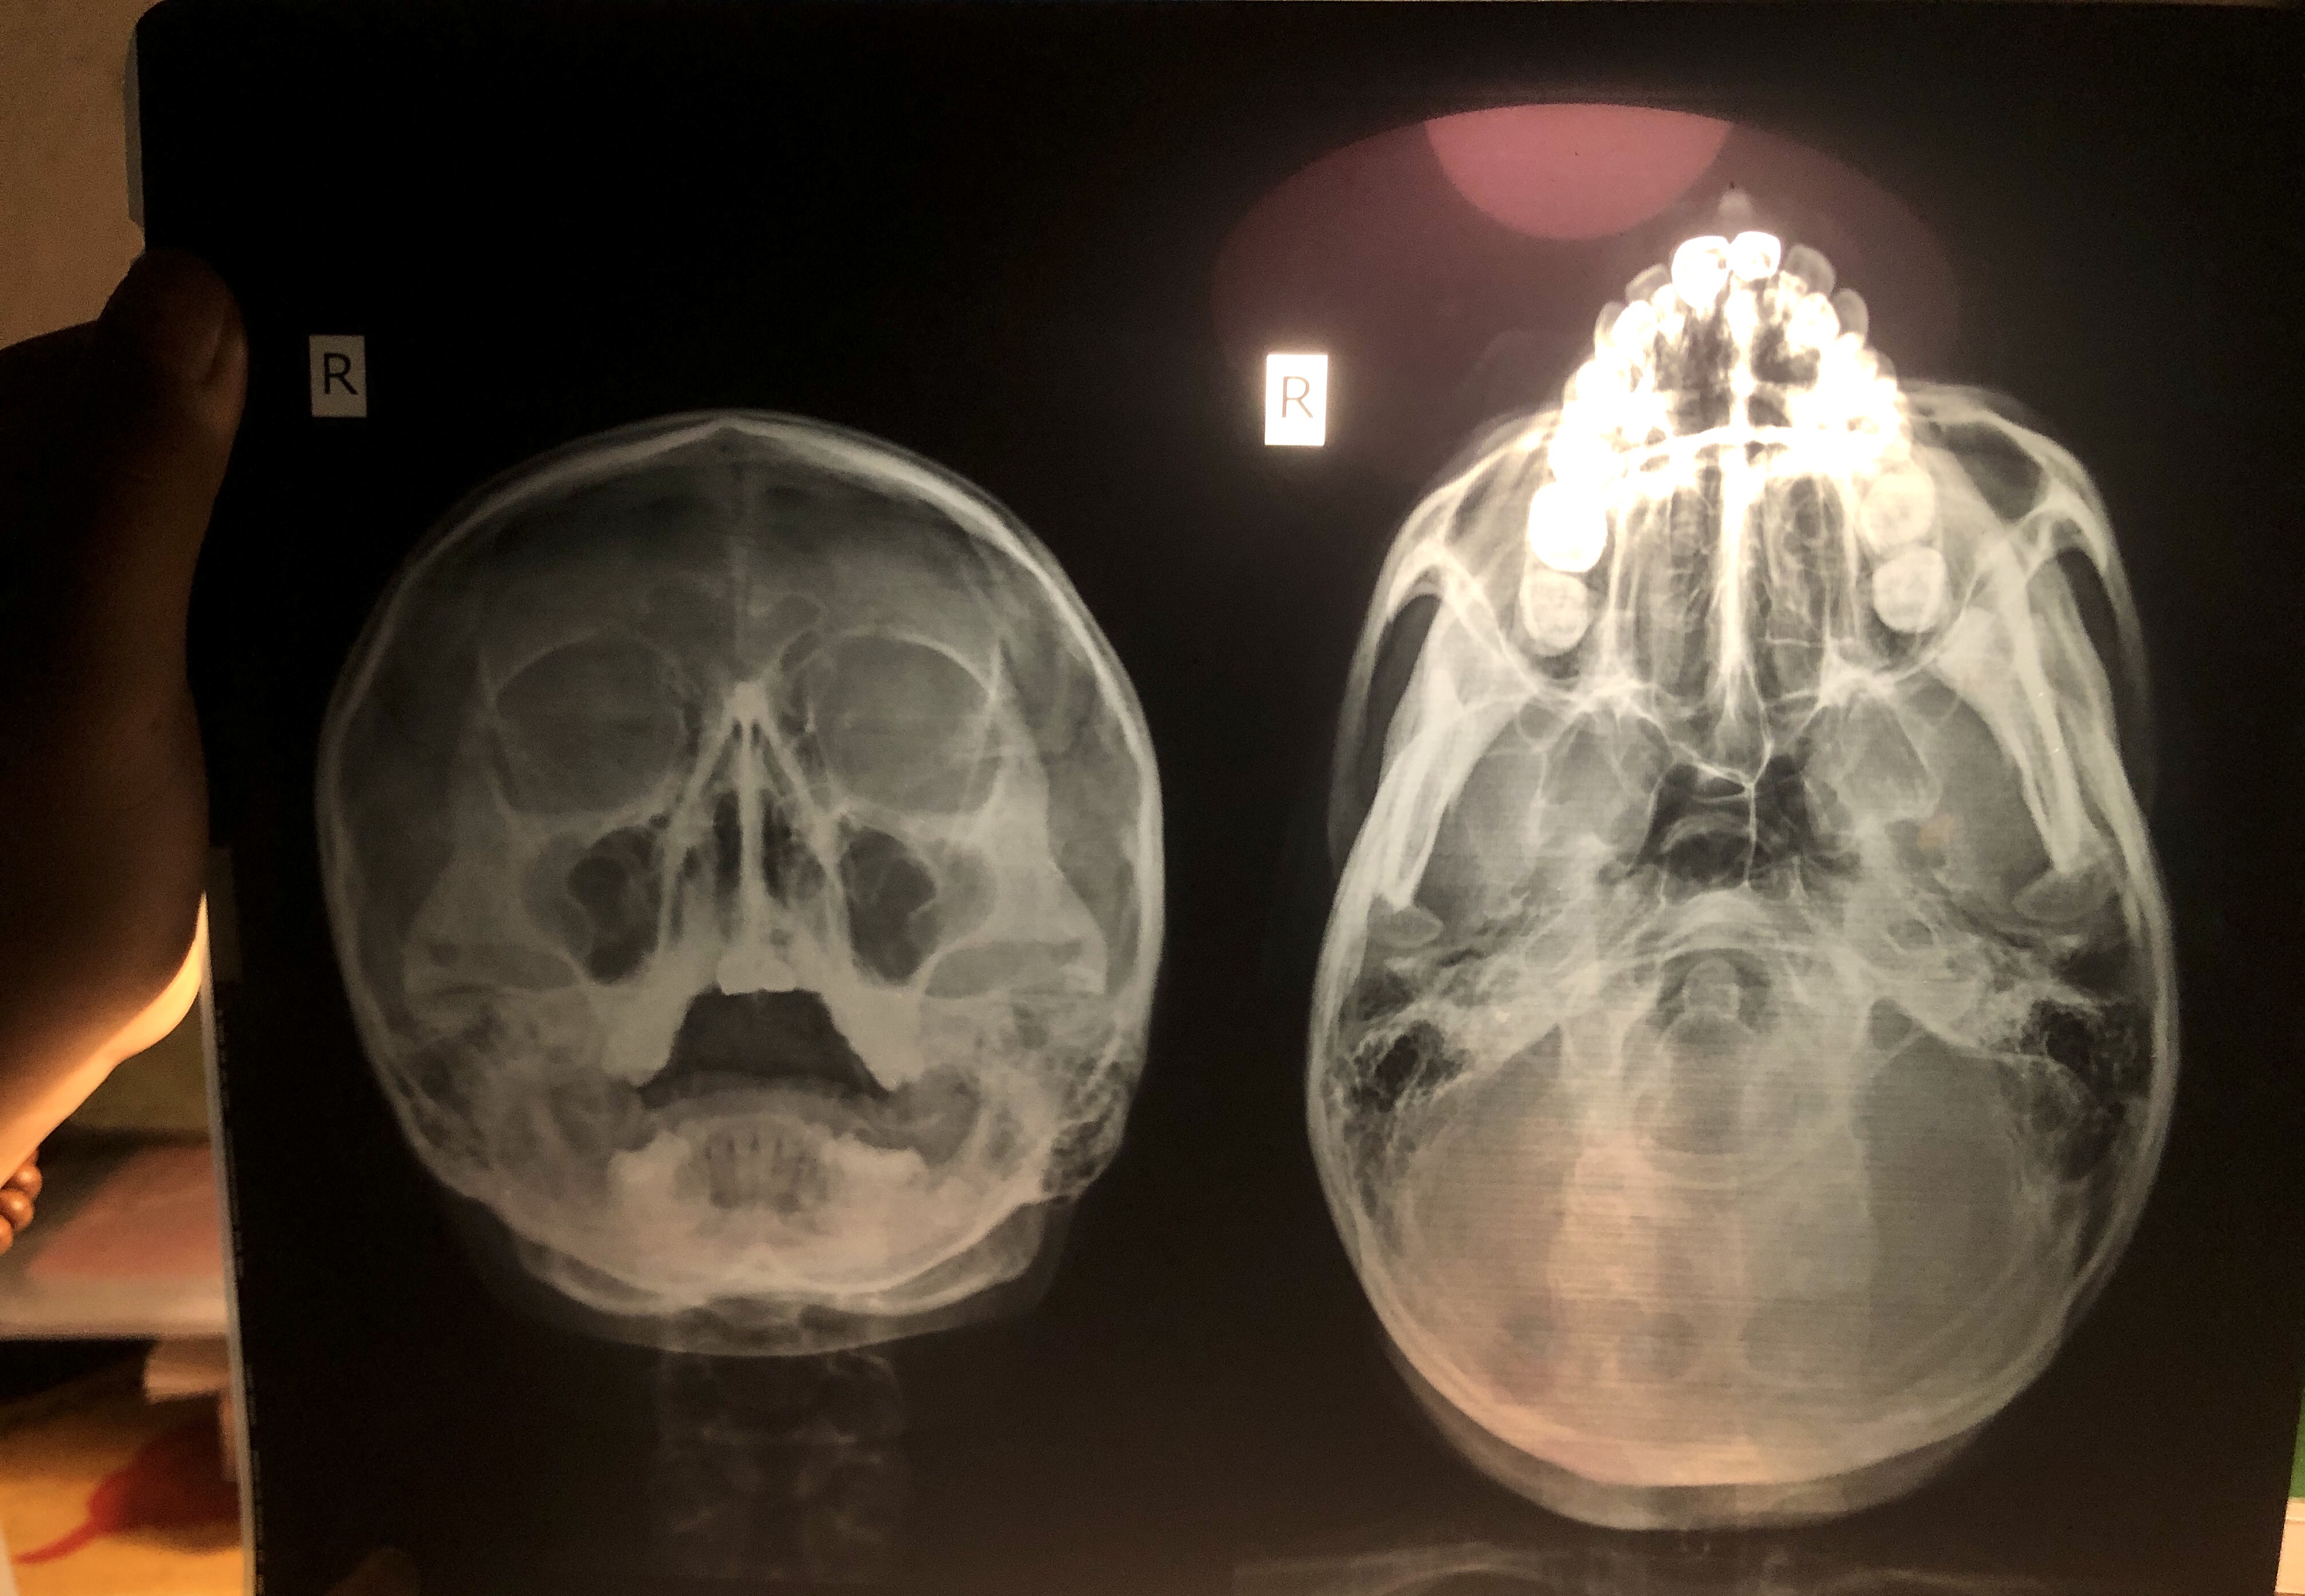

Như chẩn đoán thì em viêm tai giữa nặng và có thể có cả viêm xoang nữa. Đơn thuốc của em nên có kháng sinh và chống viêm nhưng chị chưa thấy trên ảnh em chụp. Nếu được thì em chụp thêm cho chị đầy đủ xét nghiệm và đơn thuốc điều trị nhé

Tình hình của em viêm mủ tai thì ra cơ sở nội soi tai mũi họng để hút rửa. Khi chắc chắn hơn về chẩn đoán tai mũi họng thì chị mới kê đơn kháng sinh chống viêm cho được.